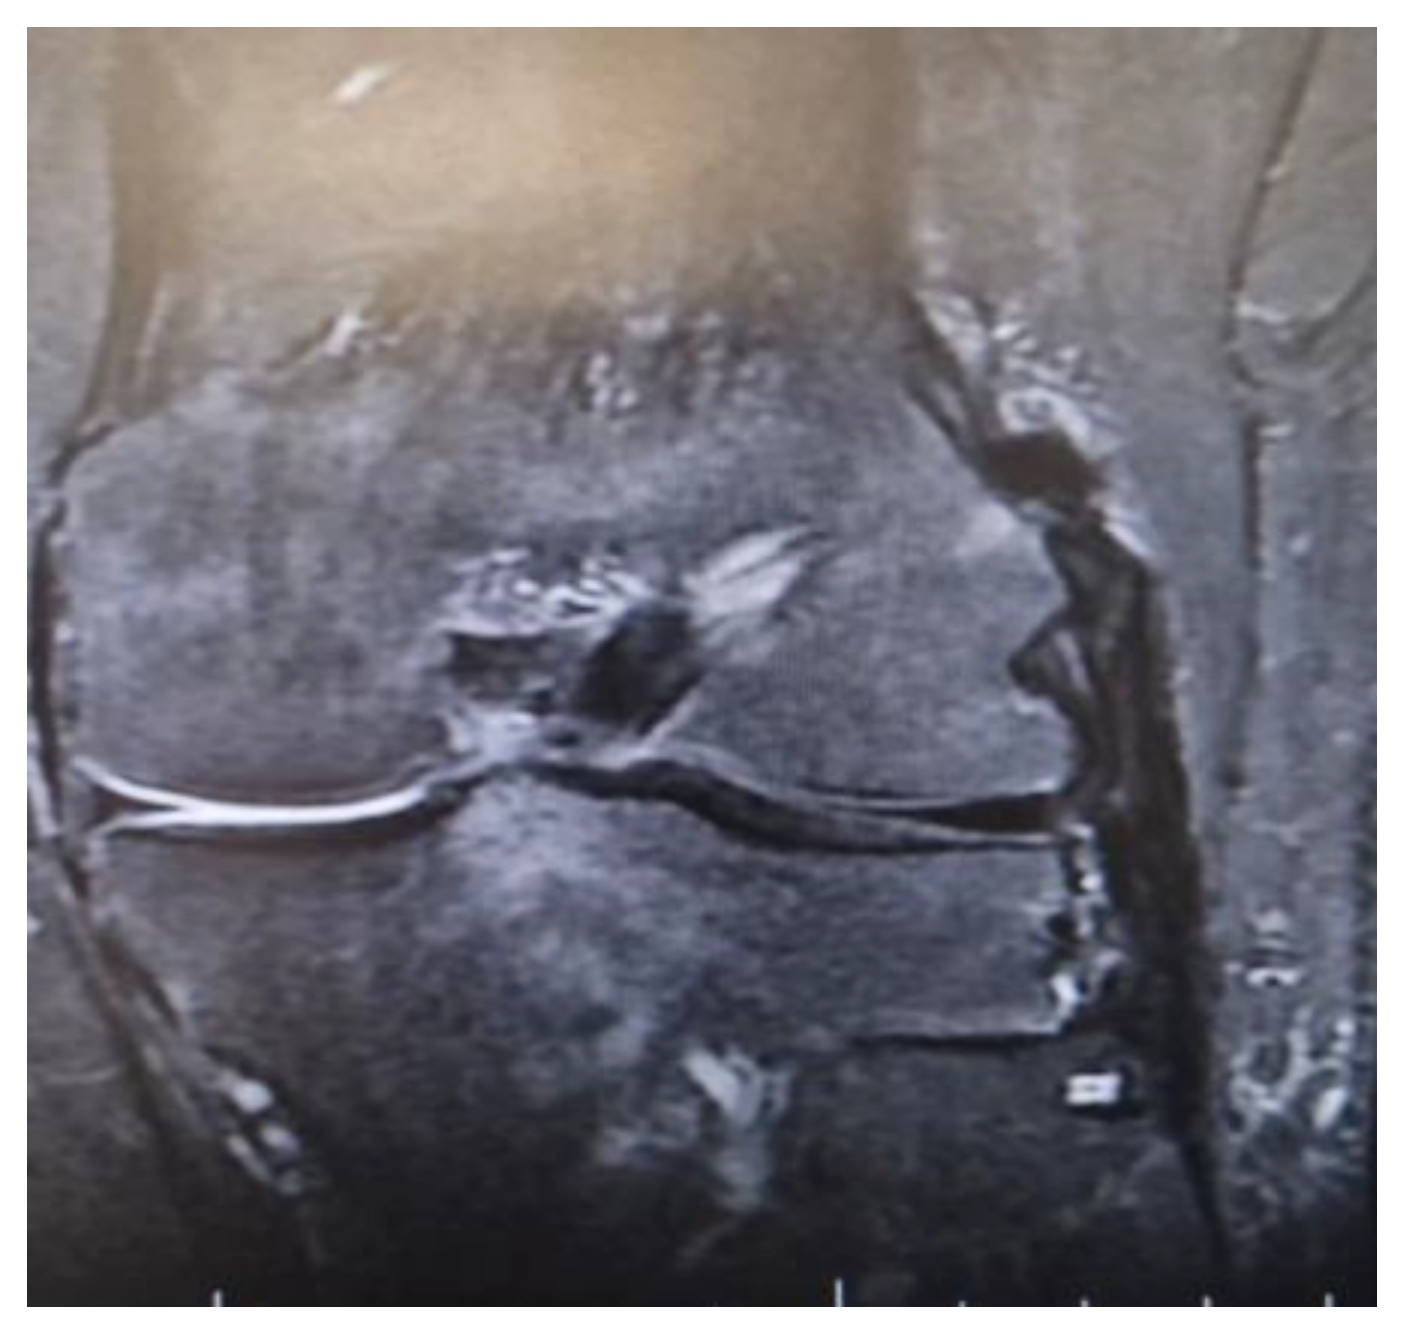

There were also a couple of cases on which a single Achilles allograft was used to reconstruct both the ACL and MCL or the ACL and LCL and ALL. In the cases where the ACL and MCL were reconstructed, the ACL was reconstructed in a standard manner, with the Achilles bone block on the femoral condyle, and after fixing the graft in the tibial tunnel, the remaining allograft was used to reconstruct the MCL. When the ACL and LCL were reconstructed with a single Achilles allograft, the femoral tunnel was created in an OUTSIDE-in technique. The ACL part was fixed with screws on the femoral tunnel and the remaining Achilles allograft was split in two, on the reconstructed LCL limb and the ALL on the other (Figure 1 and Figure 2).

Figure 2.

MRI demonstrating a single Achilles allograft used to reconstruct ACL, LCL, and ALL, with clear visualization of the graft distribution.